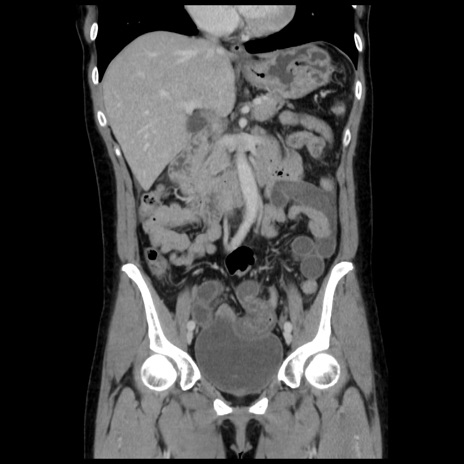

症例10(冠状断像)

【症例】 50歳代女性

【主訴】 腹痛

【現病歴】前日生レバーを食べた。今朝に排便あり。 昼前に突然発症の腹痛を生じ、当院救急外来を受診した。

【既往歴】 子宮筋腫にてで子宮全摘後

【身体所見】 意識清明、腹部:平坦、軟、下腹部やや左を中心に圧痛・反跳痛あり、筋性防御あり

【データ】WBC 7800、CRP 0.07